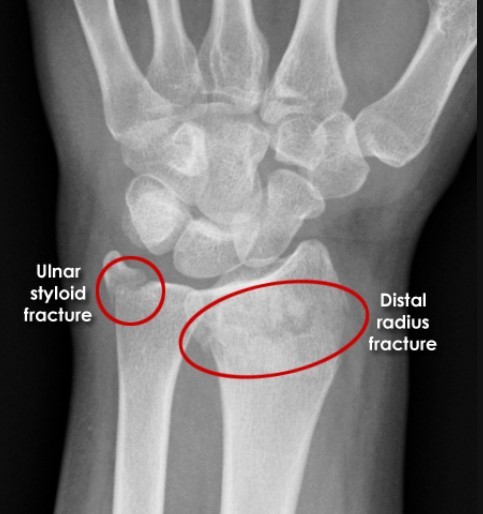

Patient reports to A+ E following a FOOSH. The arm shows dorsal displacement of the distal radius. X ray of the arm is shown below. What is the likely diagnosis?

Colle’s fracture

Dorsally Displaceed Distal radius / Dinner fork Deformity